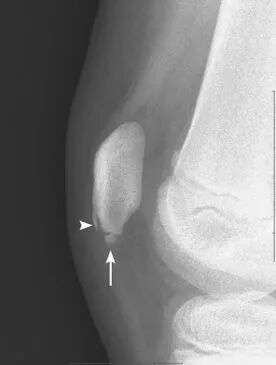

图3 髌骨下极存在撕脱性骨折(长箭头所示)。可见轻度软组织肿胀。髌骨前方的高密度影是一个骨化中心(箭头端所示)。

Sinding-Larsen-Johansson 病的影像学表现包括在髌骨下缘出现副骨化中心或撕脱骨片,并伴有软组织肿胀(图3)。其在X线片和磁共振成像(MRI)上的表现基本上与髌骨袖套状骨折难以区分,鉴别诊断依赖于临床病史和体格检查。